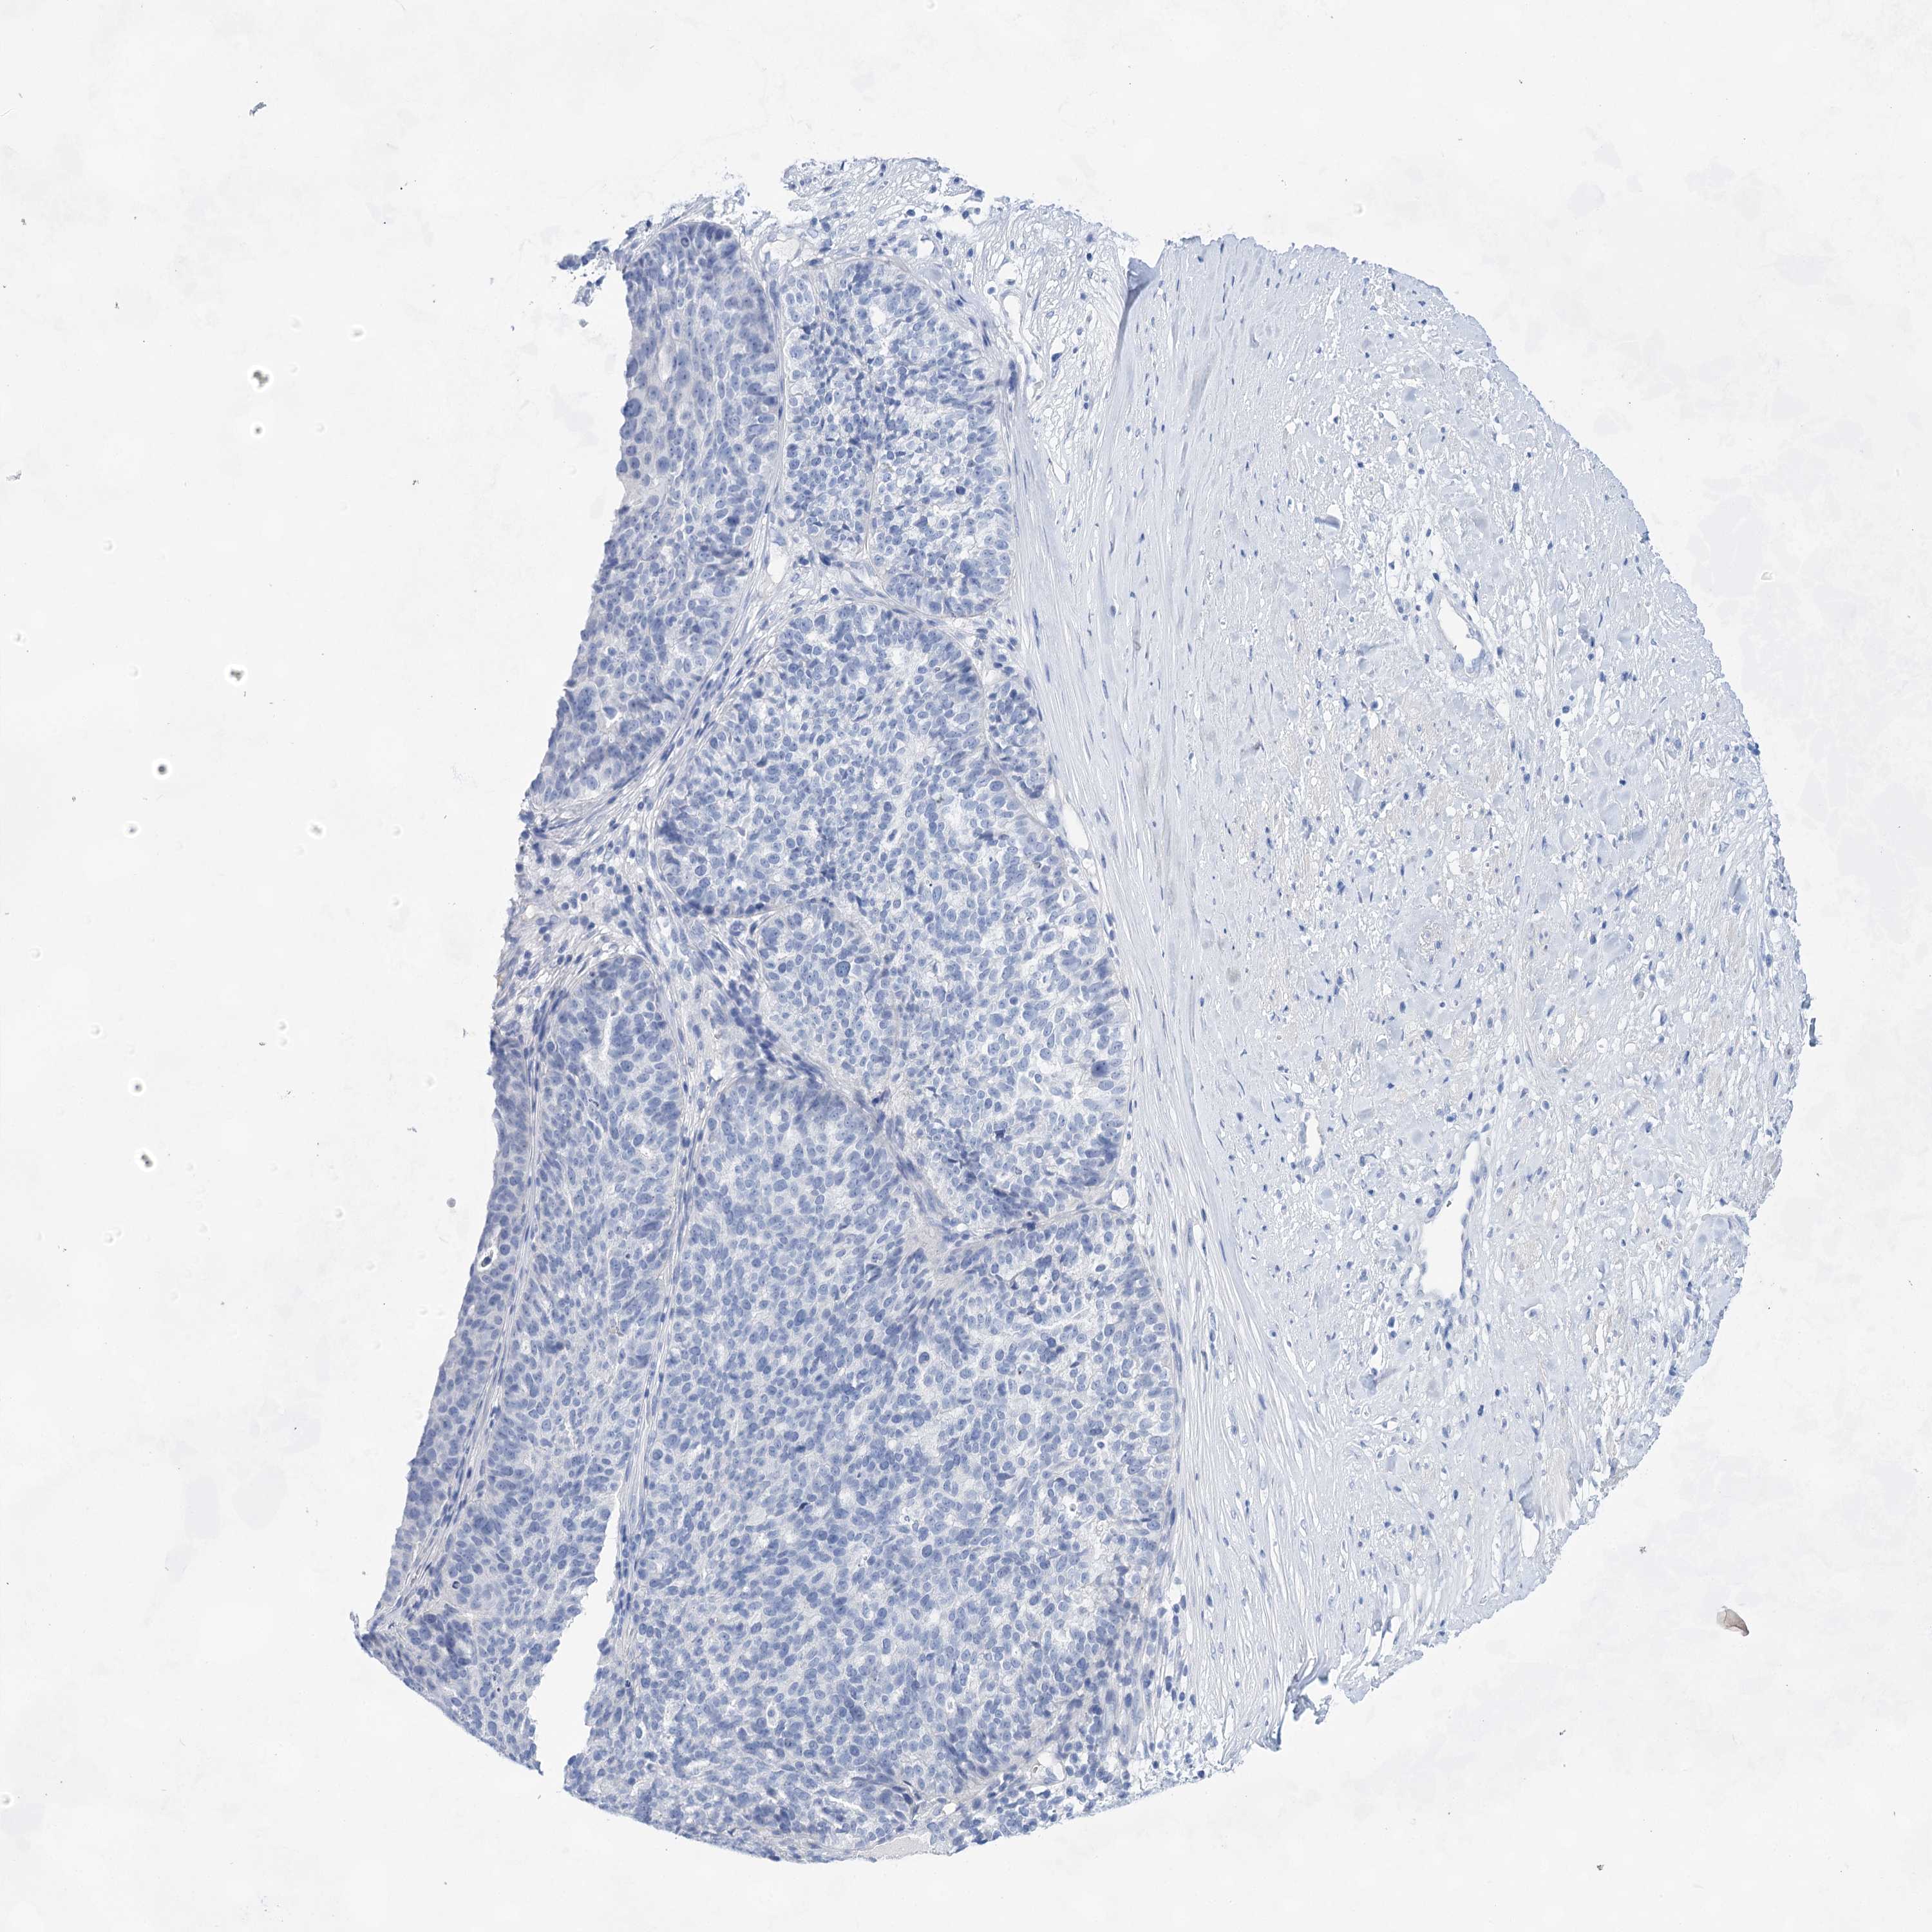

OVARIAN CANCER - Protein expressioni

A mouse-over function shows sample information and annotation data. Click on an image to view it in a full screen mode. Samples can be filtered based on level of antibody staining by selecting one or several of the following categories: high, medium, low and not detected. The assay and annotation is described here.

Note that samples used for immunohistochemistry by the Human Protein Atlas do not correspond to samples in the TCGA dataset.

Antibody stainingi

Antibody staining in the annotated cell types in the current human tissue is reported as not detected, low, medium, or high, based on conventional immunohistochemistry profiling in selected tissues. This score is based on the combination of the staining intensity and fraction of stained cells.

Each image is clickable and will lead to virtual microscopy that enables deeper exploration of all samples and also displays staining intensity scores, fraction scores and subcellular localization as well as patient and tissue information for each sample.

Antibody HPA029855

Antibody HPA029856

Antibody CAB026343

Cystadenocarcinoma, serous, NOS

Carcinoma, endometroid

Cystadenocarcinoma, mucinous, NOS

Carcinoma, NOS